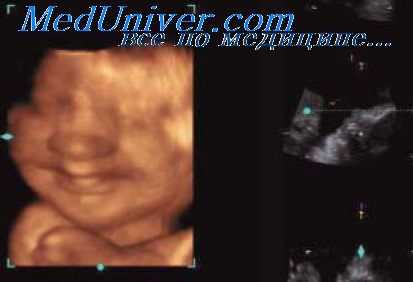

При поражении обеих бедренных костей важно тщательно исследовать лицо плода, поскольку может иметь место синдром гипоплазии бедра - необычного лица при котором будет обнаруживаться двухсторонняя гипоплазия бедренных костей, аномалии лица, такие как короткий нос с широким кончиком, длинный фильтр, микрогнатия и расщелина неба. Патология может затрагивать и другие сегменты нижней конечности (аплазия малоберцовой кости), а также верхние конечности. Данный синдром возникает спорадически и имеет связь с наличием сахарного диабета у матери. В литературе имеются указание на семейные формы заболевания, а также на возможность его пренатальной диагностики.